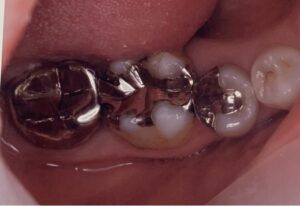

内容としては、部分的に歯を覆うセラミックインレー(素材:エナミック)と全体を覆うセラミッククラウン(素材:ジルコニア)が半々といったところです。

当院で行っている部分的な虫歯や銀歯のやりなおしなどの治療には、エナミックというセラミックを用いています。これはドイツの大手メーカーVITAという会社が2012年ごろより販売しているセラミックです。

先ほどから書いてきたジルコニアを部分的なセラミックインレーに使用することも実はできます。しかし、当院では使用しておりません。

部分的なインレーの場合、かむ面にどうしてもセラミックと歯の部分が両方あることになり、その継ぎ目がかむ面にできてしまうことは構造上しょうがないことです。

セラミックインレーは、以上の理由により実はセラミッククラウンより難しいと歯科医のなかでは言われています。削る量は少なくてすむのですが、一般的にはやりなおしが非常に多い治療です。